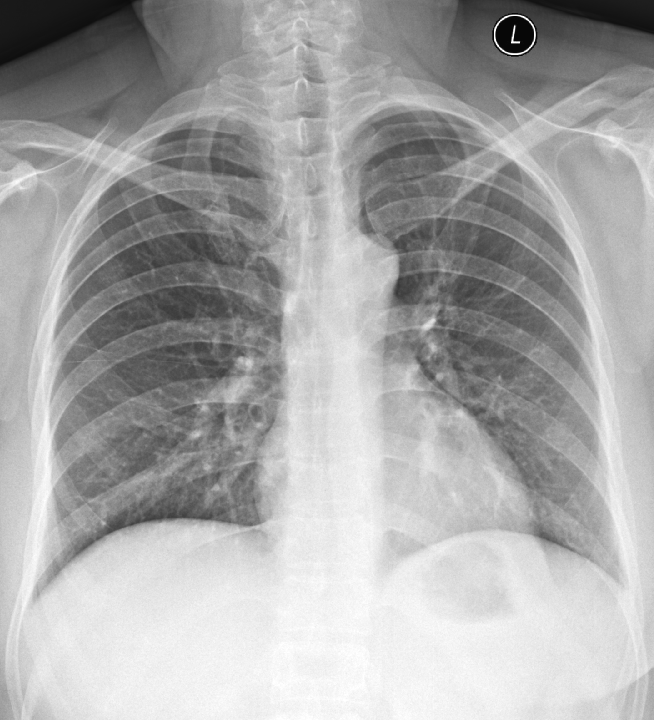

動態(tài)平板DR攝影系統(tǒng)在對胸部的攝影檢查中能夠高清晰度顯示肺組織的結(jié)構(gòu),為肺部疾病提供了有價值的科學依據(jù)。

c、胸部

適應癥:氣管支氣管病變;肺部病變(先天性發(fā)育異常、炎癥、結(jié)核、腫瘤、寄生蟲病變等);心臟病變(心包積液、心包炎、先天及后天性心血管病等);胸膜病變(胸膜炎、胸膜腫瘤等);縱膈病變(氣腫、腫瘤等)。